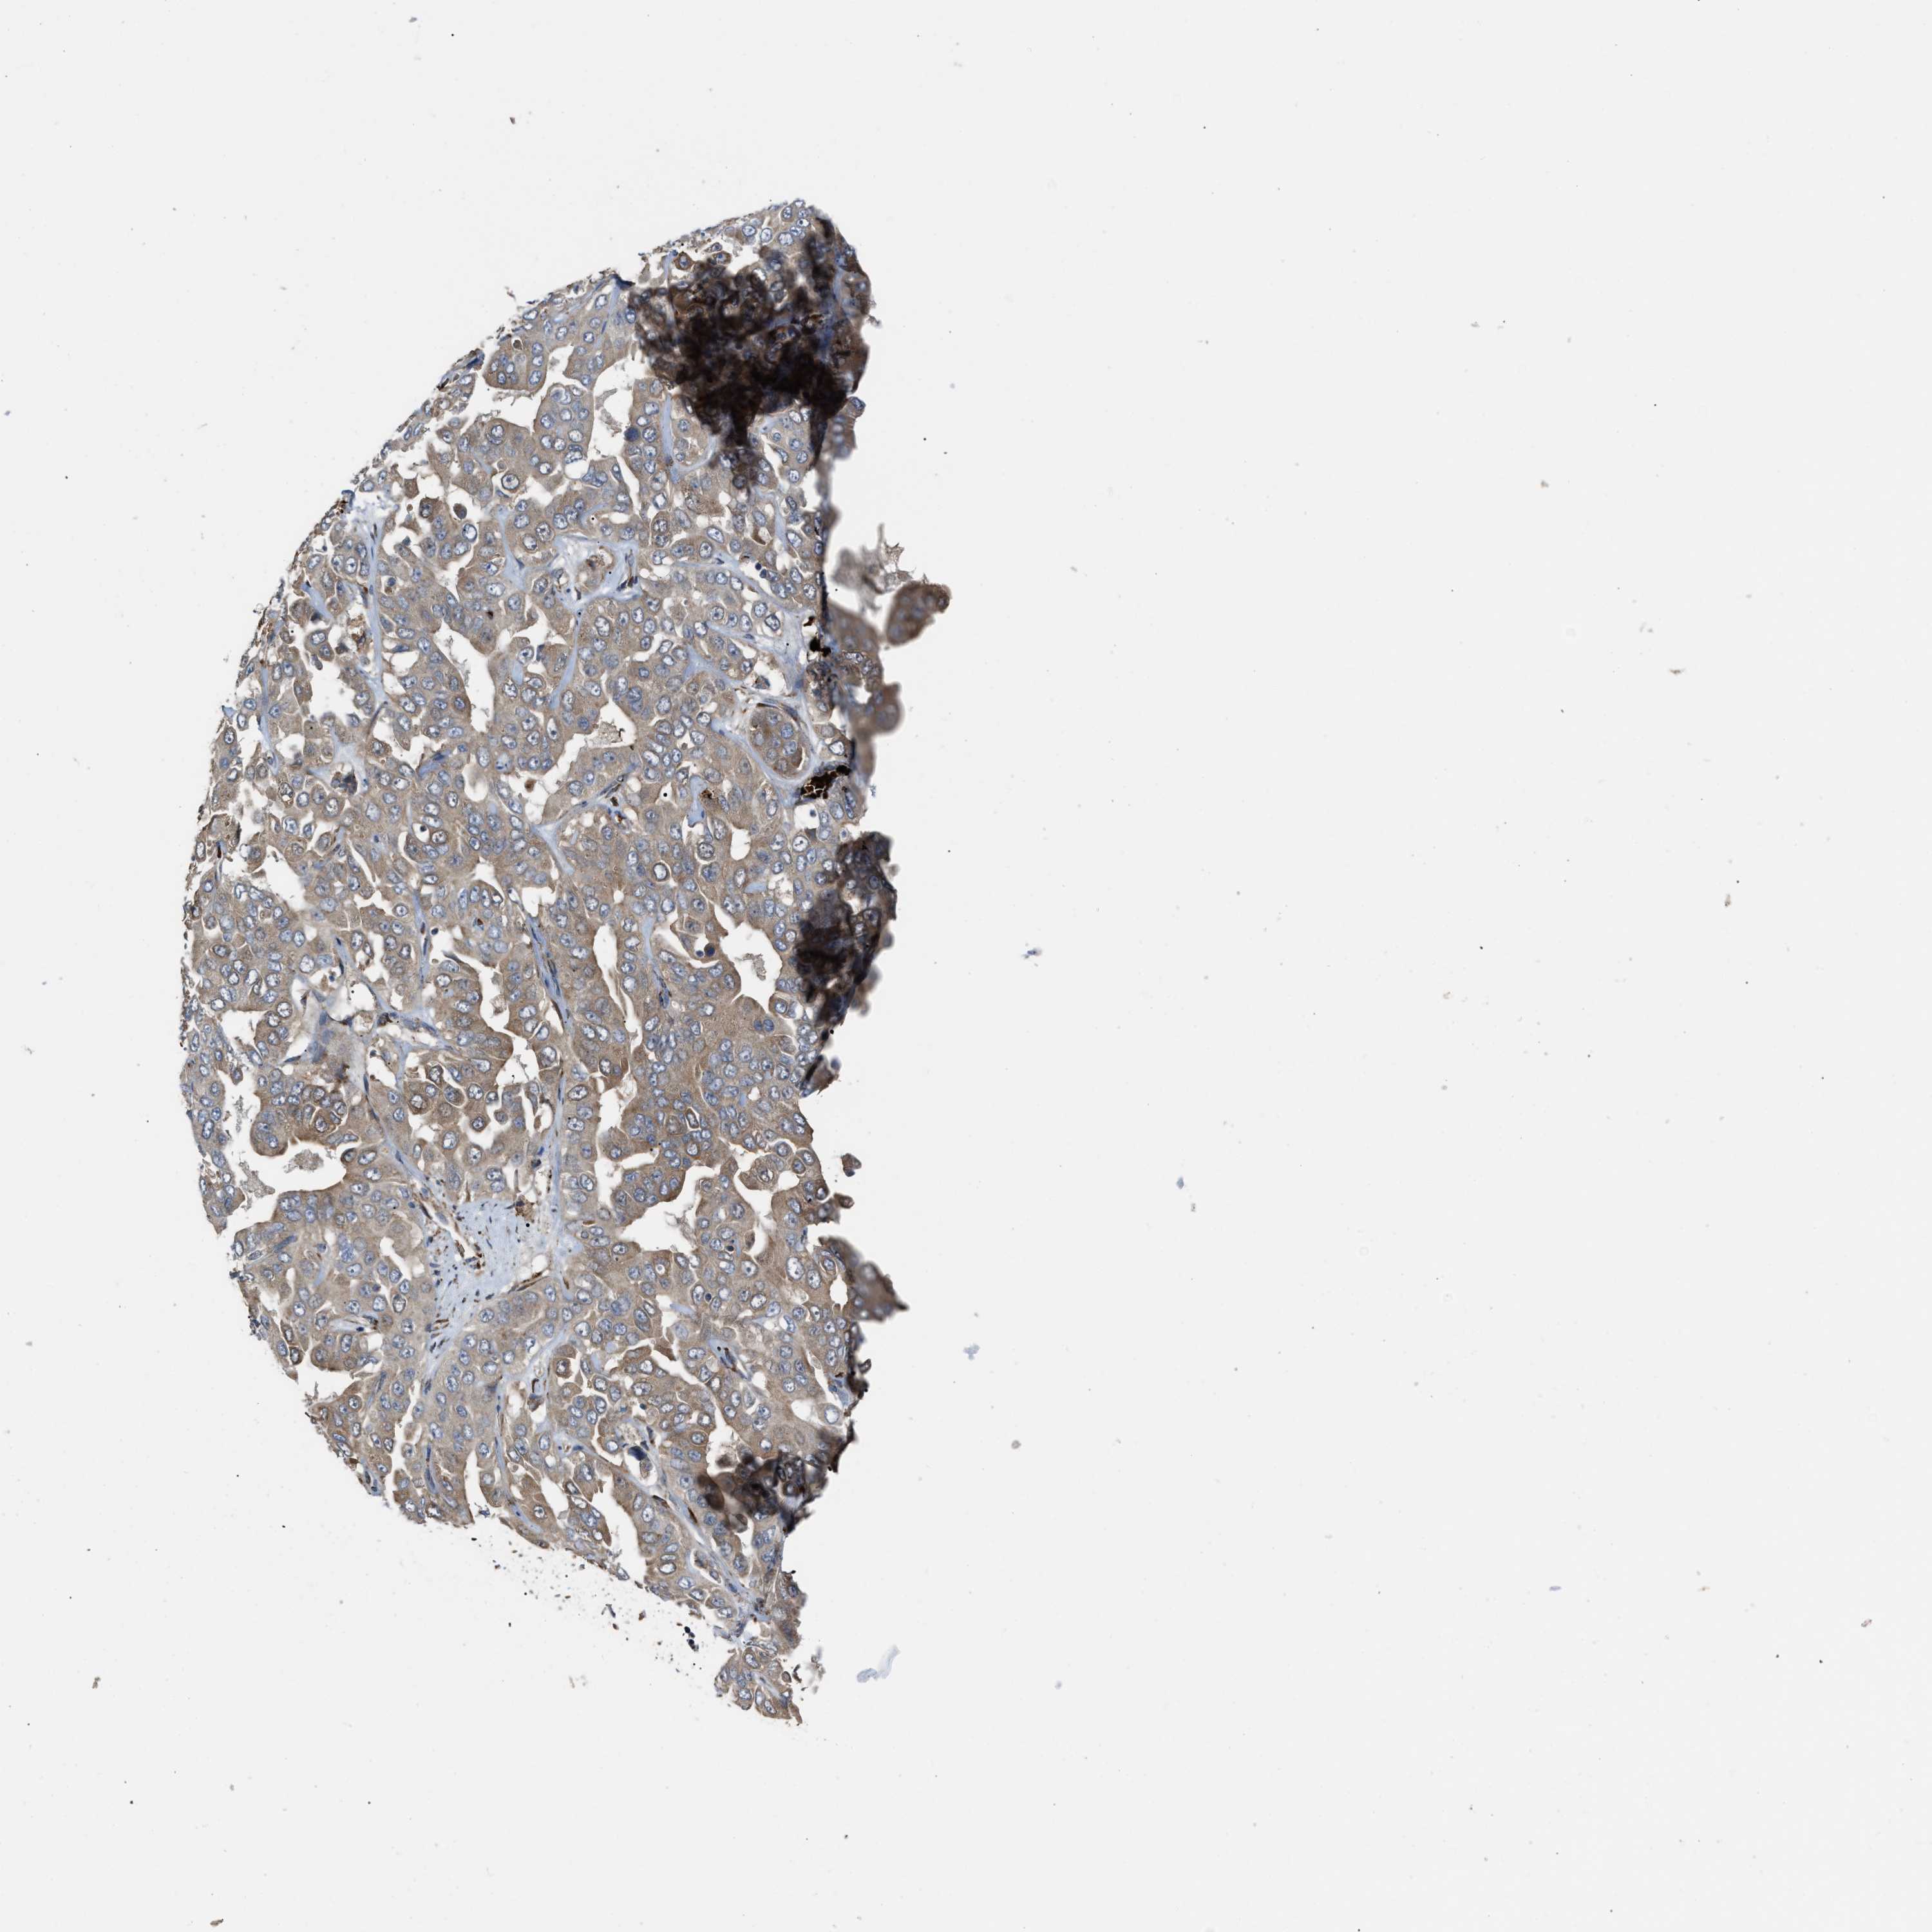

LIVER CANCER - Protein expressioni

A mouse-over function shows sample information and annotation data. Click on an image to view it in a full screen mode. Samples can be filtered based on level of antibody staining by selecting one or several of the following categories: high, medium, low and not detected. The assay and annotation is described here.

Note that samples used for immunohistochemistry by the Human Protein Atlas do not correspond to samples in the TCGA dataset.

Antibody stainingi

Antibody staining in the annotated cell types in the current human tissue is reported as not detected, low, medium, or high, based on conventional immunohistochemistry profiling in selected tissues. This score is based on the combination of the staining intensity and fraction of stained cells.

Each image is clickable and will lead to virtual microscopy that enables deeper exploration of all samples and also displays staining intensity scores, fraction scores and subcellular localization as well as patient and tissue information for each sample.

Antibody HPA019601

Antibody CAB008667

Staining

High

Medium

Low

Not detected

Intensity

Strong

Moderate

Weak

Negative

Quantity

>75%

75%-25%

<25%

None

Location

Nuclear

Cytoplasmic/membranous

Cytoplasmic/membranous,nuclear

Carcinoma, Hepatocellular, NOS

Cholangiocarcinoma